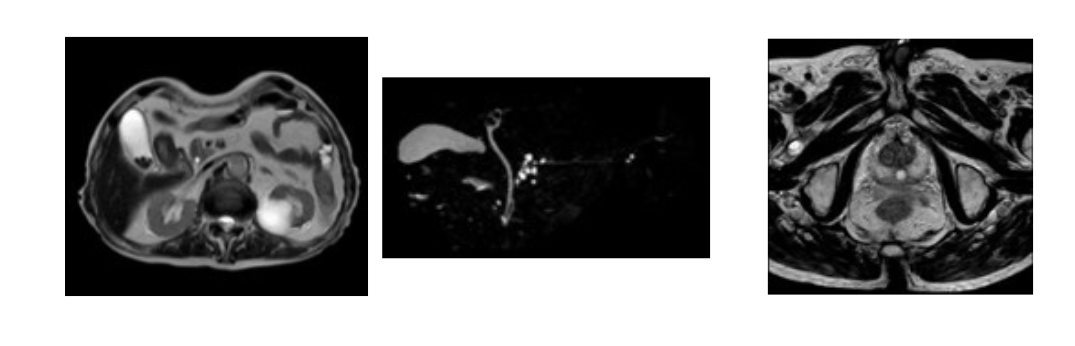

【腹部】 【前立腺】